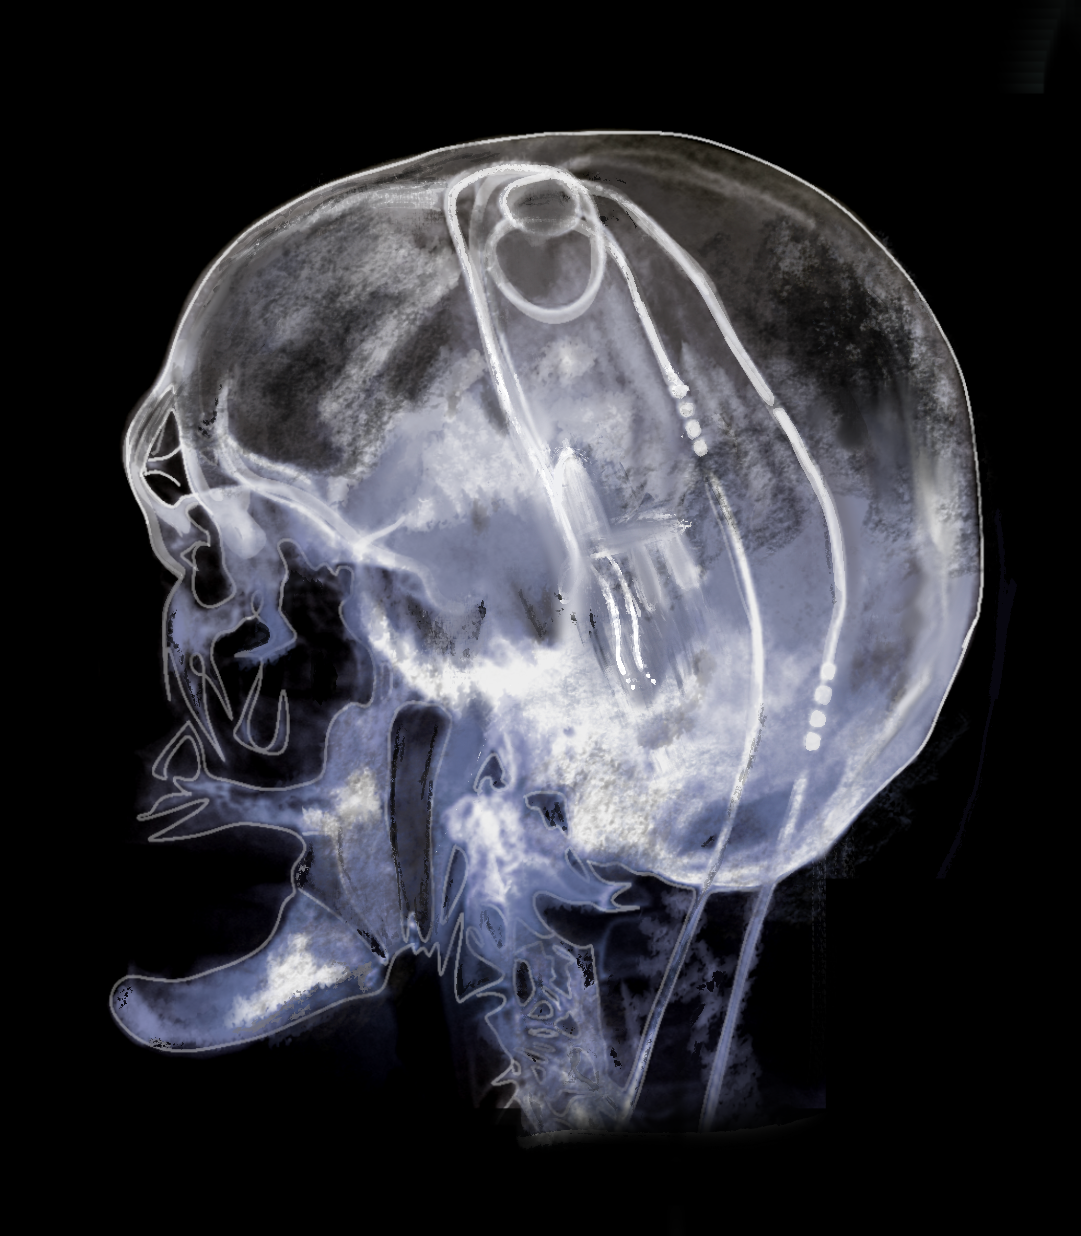

From www.dreamstime.com